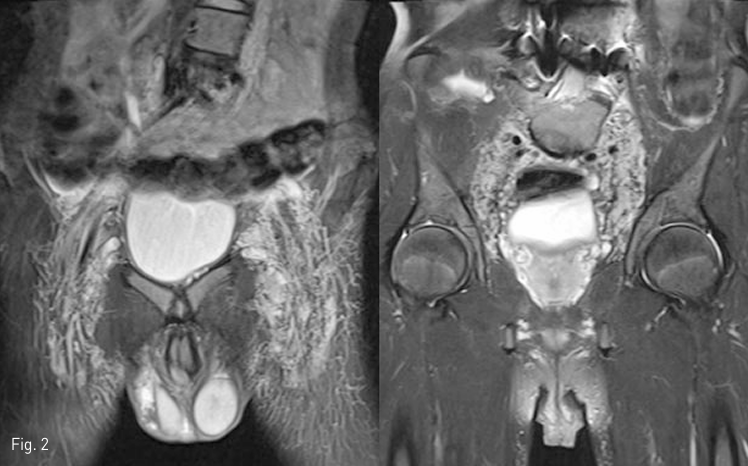

Fig 2

T2 weighted MR coronal images showed hypertrophic inguinal lymph nodes as well as lymphatic vascular structures in the pelvic retroperitoneum. Scrotal skin showed edematous change. However, there was no evidence of direct lympho-urethral fistula.

MRI T2 강조 영상에서 서혜부 림프절 및 림프관과 골반 내 장골동맥 주변 림프관의 비대 소견을 보였다 (Fig. 2). 양측 서혜부 림프절 경유 리피오돌 림프조영술에서도 상기 비대소견이 있었으나 이에 더하여 허벅지의 안쪽 및 음낭 쪽을 향하는 비정상적인 림프액의 역류가 보였다. 한편 흉관 및 좌측 쇄골하정맥으로의 림프액의 합류는 정상이었다. Spot radiography 및 C-arm CT를 이용하여 주입된 리피오돌의 분포를 정밀하게 관찰하였으나 전립선 요도에서부터 음경 요도에 이르기까지의 범위에서 비정상적인 요도-림프관 연결을 의심할 만한 소견은 보이지 않았다 (Fig. 3). 주입된 리피오돌은 음낭 피부를 거쳐서 귀두 부근의 피부 및 피하조직에 분포하고 있었다. 임상 및 검사 소견을 고려하여 누난증후군과 연관된 림프계 형성이상으로 인해 소장에서 생성된 유미 림프액이 하지, 서혜부, 음낭 피부 방향으로 역류하면서 발생한 림프부종이 있고, 압력이 높아진 림프관내 림프액이 요도로 배액되는 것 으로 진단하였다.